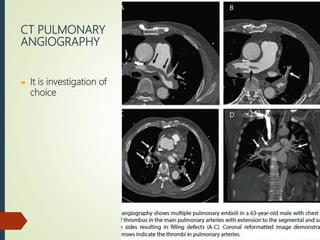

CT PULMONARY

ANGIOGRAPHY

 It is investigation of

choice

CT PULMONARY ANGIOGRAPHY